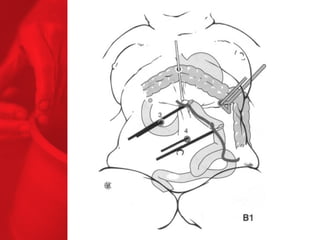

DIVERSION BILIO-PANCREATIQUE (DBP)AVEC «SWITCH DUODENAL» Procédure de malabsorption Poche de l'estomac plus grande Plus grande perte de poids Plus grande malabsorption des nutriments Perte de surcharge pondérale de 74% la première année, 78% la deuxième année, 81% la troisième année, 84% la quatrième année et 91% la cinquième année*. Diminue le diabète de type 2 chez près de 77% des patients** *Duodenal Switch: An Effective Therapy for Morbid Obesity – Intermediate Results” Baltasar A, Bou R. Obesity Surgery 2001 Feb; 11(1): 54-8. ** Buchwald H, Avidor Y, Braunwald E, et al. Bariatric Surgery—A Systematic Review of the Literature and Meta-analysis. Journal of the American Medical Association 2004 Oct 13;292(14).

COMMENT FONCTIONNE LADBP AVEC LE SWITCH DUODENAL ? Facteurs chirurgicaux Restriction du volume des repas Malabsorption élevée Facteurs pour les patients Apport en calories Dépense en calories BILAN ENERGETIQUE = apport alimentaire dépense en énergie